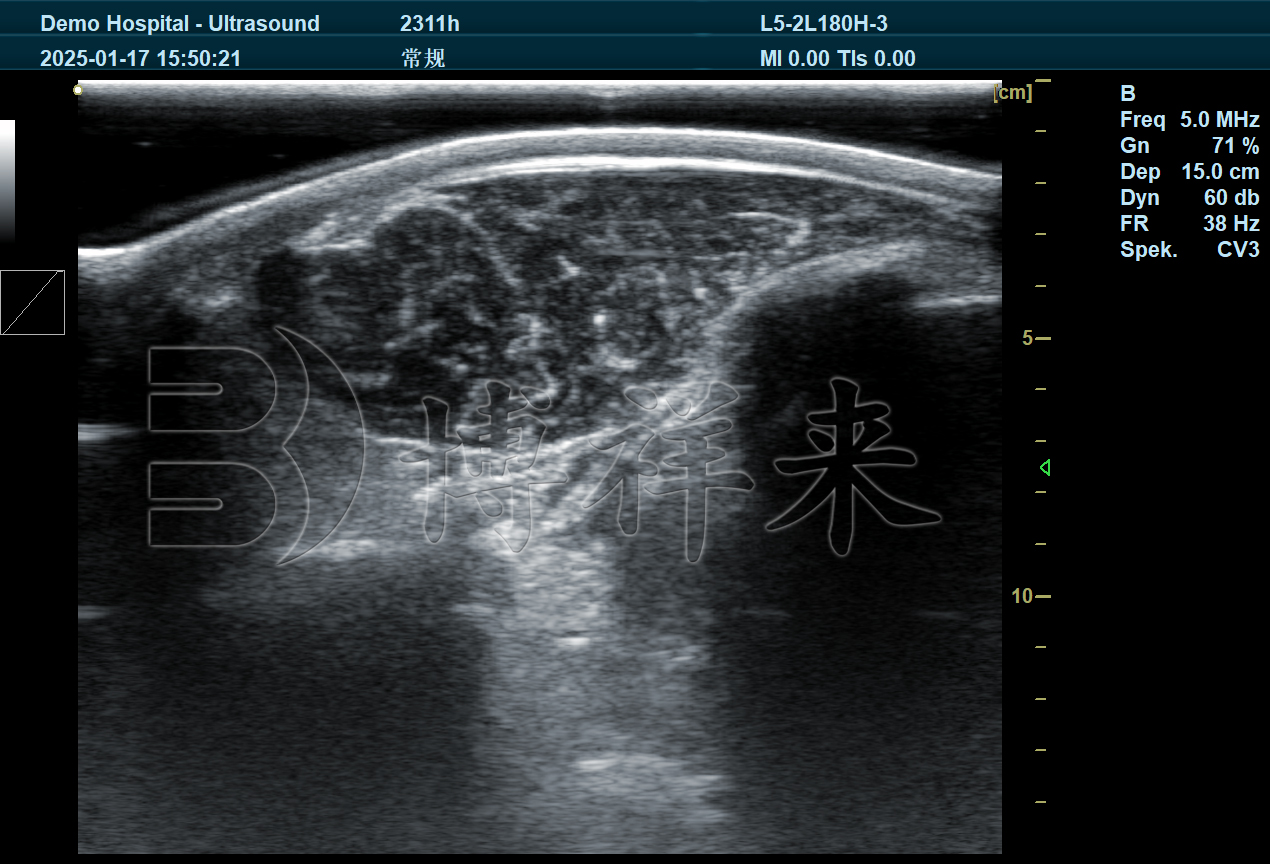

高精准度:现代超声算法针对反刍动物的特殊组织结构进行了优化,能提供高分辨率的内部结构影像,活体数据与屠宰后数据具有高度相关性。

操作便捷:测定仪可在牛只指定肋间隙快速扫描,实时显示背膘和眼肌的横截面图像,并能自动完成宽度、面积等参数的量化计算。